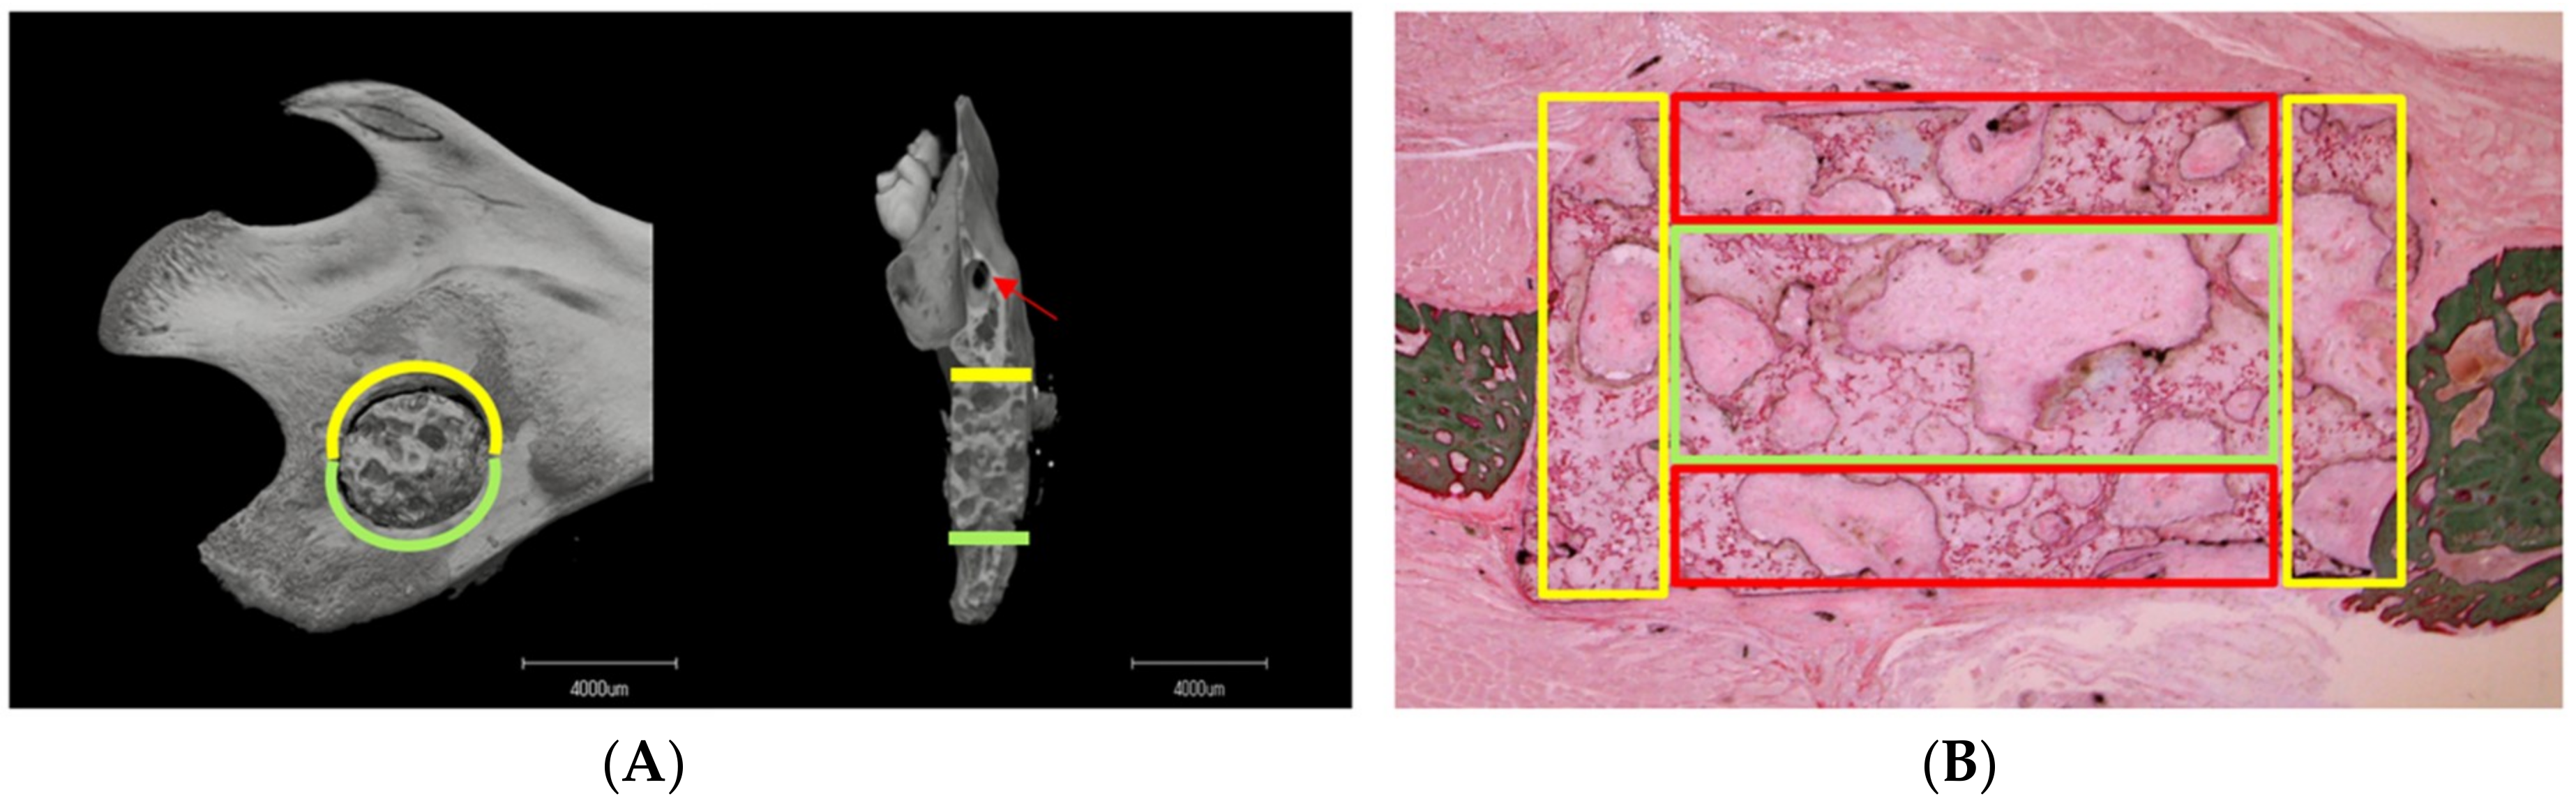

3.1. Micro-CT Analysis

3.1.1. Image Description

3.1.2. Material–Host Bone Combinations and the Quantity of Newly Formed Osteoid Tissue

3.1.3. Difference in Osteogenesis between the Superior and Inferior Sides of the Critical Mandibular Defect

3.2. VG Staining Results

3.2.1. Description of VG Staining